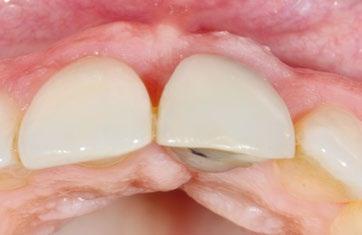

Paciente mujer de 35 años, con amplia exposición gingival en sonrisa y alta demanda estética (Fig. 1, 2).

Su solicitud inicial es volver a blanquear el 21, que había sido previamente endodonciado y había recibido sucesivos tratamientos blanqueadores que habían recidivado. Refiere ligera molestia en la papila interincisiva. En la exploración radiográfica intraoral 1 2

se aprecia una extensa reabsorción radicular interna, con el consiguiente defecto óseo, que se confirma con un CBCT (Fig. 3, 4, 5). Se informa a la paciente del riesgo de fractura espontanea. Esta solicita solucionar el problema antes de que avance más.

En estos casos es crítica la gestión de los tejidos blandos para compensar la pérdida del soporte por parte del trayecto supracrestal de la raíz con en ITC y provisionalización inmediata.

En este caso decidimos utilizar la corona natural como provisional. Se rebasa en su posición original sobre el cilindro de titanio con composite fluido y se modela el perfil crítico y subcrítico ideal. Es imprescindible acabar y pulir minuciosamente, en especial la parte subgingival, para reducir el acumulo de placa (Fig. 17, 18).

Se finaliza la sutura del CAF con la corona en posición, el trayecto supracrestal de la misma dará apoyo al injerto y al colgajo, que colgajo debe cubrir 1 mm el injerto, y quedar 1 mm más coronal del margen definitivo deseado. En la imagen oclusal se ve la correcta salida del tornillo protésico y el volumen vestibular (Fig 19).

Tras 4 meses (Fig. 20, 21), se inicia la fase final de acondicionamiento mediante adición de composite a la corona provisional, presionando sobre el tejido ya maduro hasta modelar la emergencia simétrica a su contralateral, durante 2 meses más (Fig. 22).